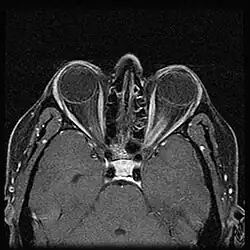

When ONSM is suspected, MRI of the brain or orbits should be performed. This will usually show characteristic findings and confirm the diagnosis.[5]